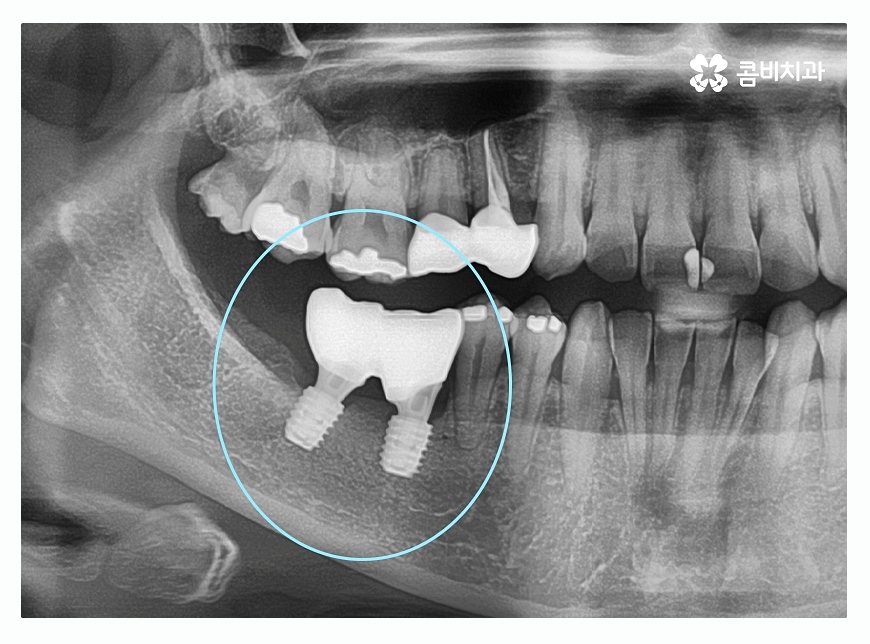

오늘 보시는 환자분의 경우에는 치주질환이 심해져서

여러 치아를 발치하게 된 사례로 자연치아의

수명을 다하지 못한 채 발치를 하는 것은 안타까운 일이지만

치주질환 관리를 제대로 하지 못할 경우에는

노년에 이르러 치아를 모두 상실하게 되는 경우도

많기 때문에 중년 이후에는 특히 주의할 필요가 있어요.

위 이미지에서 보시는 것처럼 치주염으로 인하여

잇몸뼈가 많이 내려간 경우 음식물이 잘 끼고 관리가 잘 안되면서

치아가 깊게 뿌리내리지 못해 흔들리게 되고

치아가 제대로 된 기능을 하지 못하여 발치까지 진행되는 경우가 있는데

위 환자분도 사랑니가 이런 경우에 해당되어 발치를 진행한 사례라고 할 수 있어요.